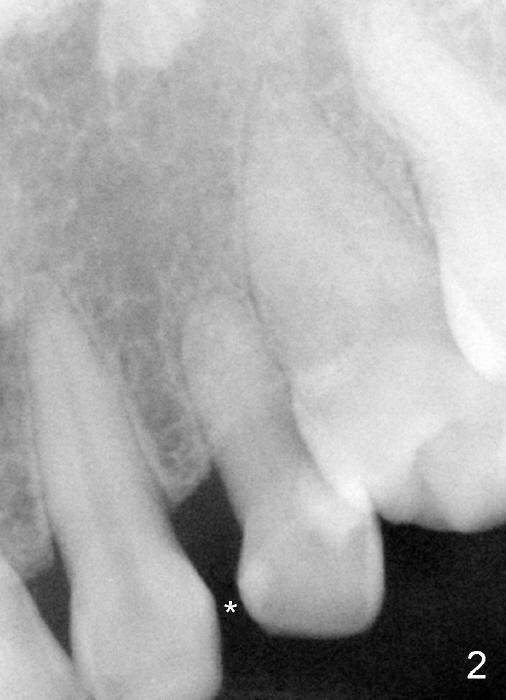

The upper left deciduous canine of a lady in her early forties looks functional 9 and 5 years ago (Fig.1,2). She wanted to close the diastema mesial to the deciduous tooth (Fig.2 *). The tooth was prepared for a provisional (Fig.3 P) and definitive restoration (Fig.4 C). The tooth becomes mobile 4 years post cementation (Fig.5).